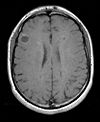

Registration Results

Unregistered baseline data: PD vs. T1Gd Unregistered baseline data: PD vs. T1Gd

Unregistered followup data: PD exam 2 vs. exam 1 Unregistered followup data: PD exam 2 vs. exam 1

Registered baseline data Registered baseline data

Registered followup data Registered followup data

Lesion change via subtraction imaging of co-registered PDLesion change via subtraction imaging of co-registered PD